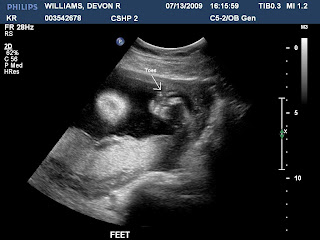

Baby Williams is the length of a spaghetti squash (about 11 inches) and almost 1 lb. Her lips, eyelids and eyebrows are more distinct, and she's developing tiny tooth buds beneath her gums. Her eyes have formed, but her irises still lack pigment.